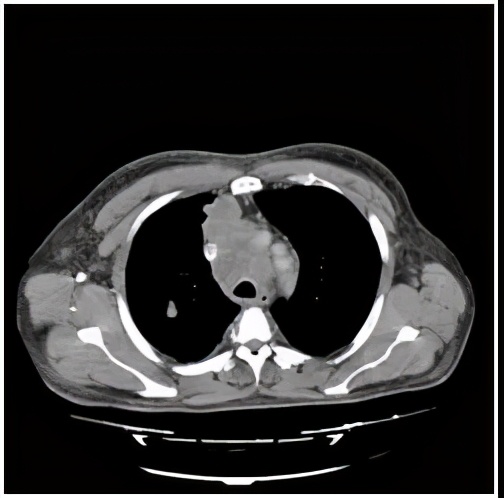

纵隔转移淋巴结图